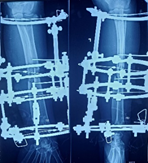

Case-II

26 years, male;

Re-fracture shaft of femur with bending plate and quiescent type infection. H/0-fall (Figure 5-10)

Figure 5 Post-operative x-ray after Plate Osteo-synthesis.

Figure 6 X-ray after re-fracture due to fall.

Figure 7 Post-operative x-ray after mount ilizarov frame kept plate in situ.

Figure 8 X-ray after removal of plate and consolidation.